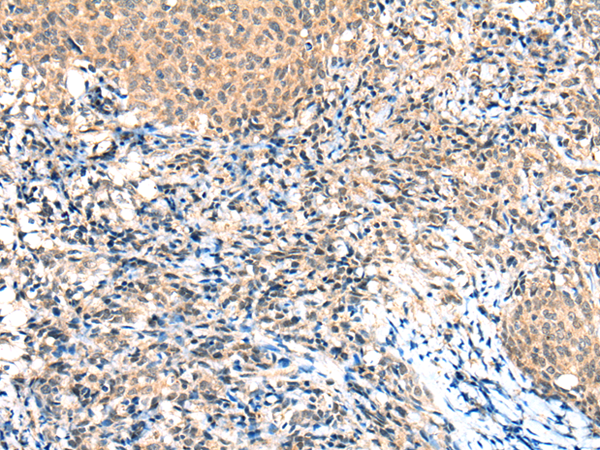

分类: 科研抗体货号: P11271别名: SMRT; TRAC; CTG26; SMRTE; TRAC1; N-CoR2; TNRC14; TRAC-1; SMAP270; SMRTE-tau应用: IHC反应种属: Human